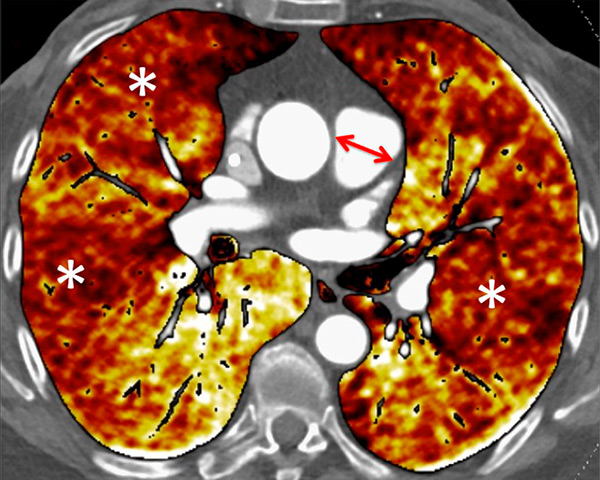

Nowadays, DECT imaging can be used for pathologies other than CTEPH and seems to offer advantages for PH characterisation because different DECT findings have been described in acute pulmonary embolism, CTEPH and idiopathic PAH (IPAH). In fact, perfusion defects are smaller and less defined in PAH than in CTEPH. This is likely due to focal under- and overperfusion as a result of the structural pulmonary vascular changes that occur in PH, which include vascular endothelial damage, cellular proliferation and occlusion in the distal pulmonary vasculature. Perfusion heterogeneities in DECT imaging are also common and seen in most cases of PAH. Findings of perfusion inhomogeneities related PAH have long been recognised in scintigraphy, and often are referred to as having a “mottled” pattern [42]. These perfusion defects are different from those seen in CTEPH, with nonsegmental and poorly defined defects (fig. 5). This heterogeneity is related to the severity of the disease. In PAH, this perfusion variability on scintigraphy is well correlated with pulmonary vascular resistance, as Talwar et al. showed [43]. Recently, similar results were published for DECT techniques (fig. 6). Ameli-Renani et al. described an increased enhancement of pulmonary arteries with reduced iodine lung perfusion in PH, and a good correlation of DECT perfusion heterogeneities with pulmonary vascular resistance; they showed a greater heterogeneity in parenchymal iodine maps in PH without pulmonary embolism [13]. The authors concluded that perfusion heterogeneities seen in DECT appear to be a direct reflection of pulmonary vascular resistance.

Figure 6

Perfusion heterogeneities in idiopathic pulmonary artery hypertension (stars) in two different patients (A/B). The dilatation of the arteries in pulmonary hypertension (arrows) is not always observed depending on the severity of pulmonary hypertension.